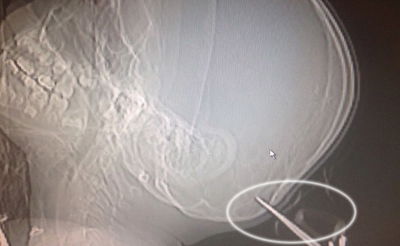

מדהים: ילד בן שבע ששיחק בביתו, מצא את עצמו עם מספריים - שאחותו זרקה עליו - נעוצות עמוק בראשו. בבית החולים הוציאו את המספריים בזהירות, ורק בנס הן לא גרמו לדימום מוחי (חדשות)